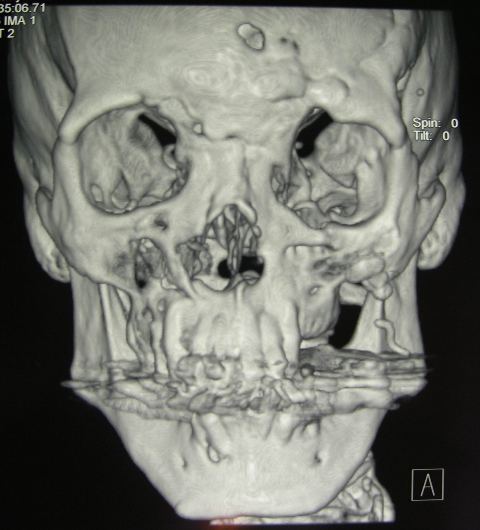

Že približno desetletje je mogoče s posebno tehniko izdelati model skeleta pacienta (zgornje ali spodnje čeljusti, lahko tudi cele lobanje) ter nato na modelu simulirati poseg in izbrati ustrezen material za operacijo. Posebna naprava s pomočjo laserskega žarka na podlagi podatkov, pridobljenih s CT-preiskavo, obdeluje tekočo snov, ki se pod vplivom laserske svetlobe strdi. Gre za metodo stereolitografije, ki jo opravljajo v tujih centrih, vendar je cena povsem sprejemljiva in kadar se pri pacientu načrtuje obsežnejša rekonstrukcija obraza (največkrat zaradi nezdravljenih ali slabo zdravljenih poškodb ter zaradi prirojenih anomalij obraznega skeleta), je model pacientovega obraznega skeleta nadvse koristen (sliki 6 in 7).

Slika 6: 3D-rekonstrukcija CT-posnetkov obraznega skeleta

Slika 7: Stereolitografski model lobanje, pridobljen na podlagi CT-posnetkov